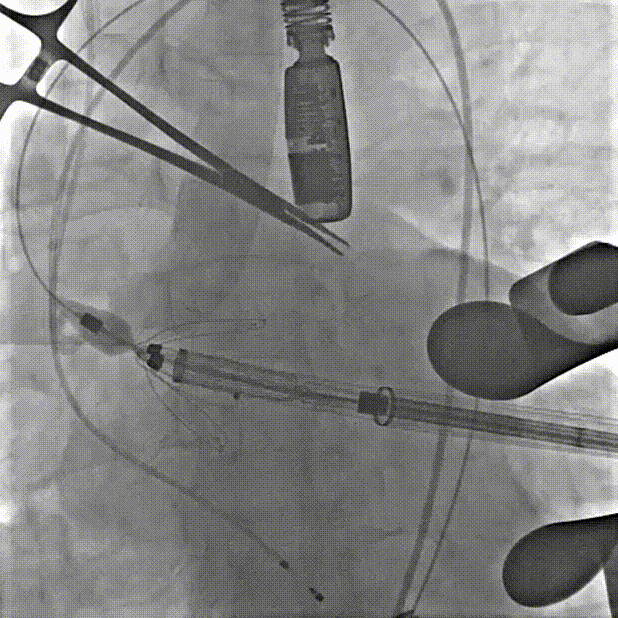

手术过程中,团队严格按照标准操作流程实施。自介入器械导入至瓣膜释放完成,器械用时约10钟。整个过程中,手术团队通过右冠窦居中造影、定位件入窦确认、释放后联合超声与造影评估,确保了瓣膜定位精准、释放平稳。术中超声评估显示无瓣周漏,血流动力学表现良好,手术过程顺利。

第一枪造影,右窦无窦重合,三窦显示不清

调整角度后造影,右窦居中位置

心尖穿刺建立轨道、单弯导管引导跨弓

定位件跨瓣打开,调整右窦定位件位置,下拉入窦

造影确认定位件入窦底

释放瓣膜

在心室中关闭外鞘、撤出输送系统

最后一枪造影,基本无瓣周漏